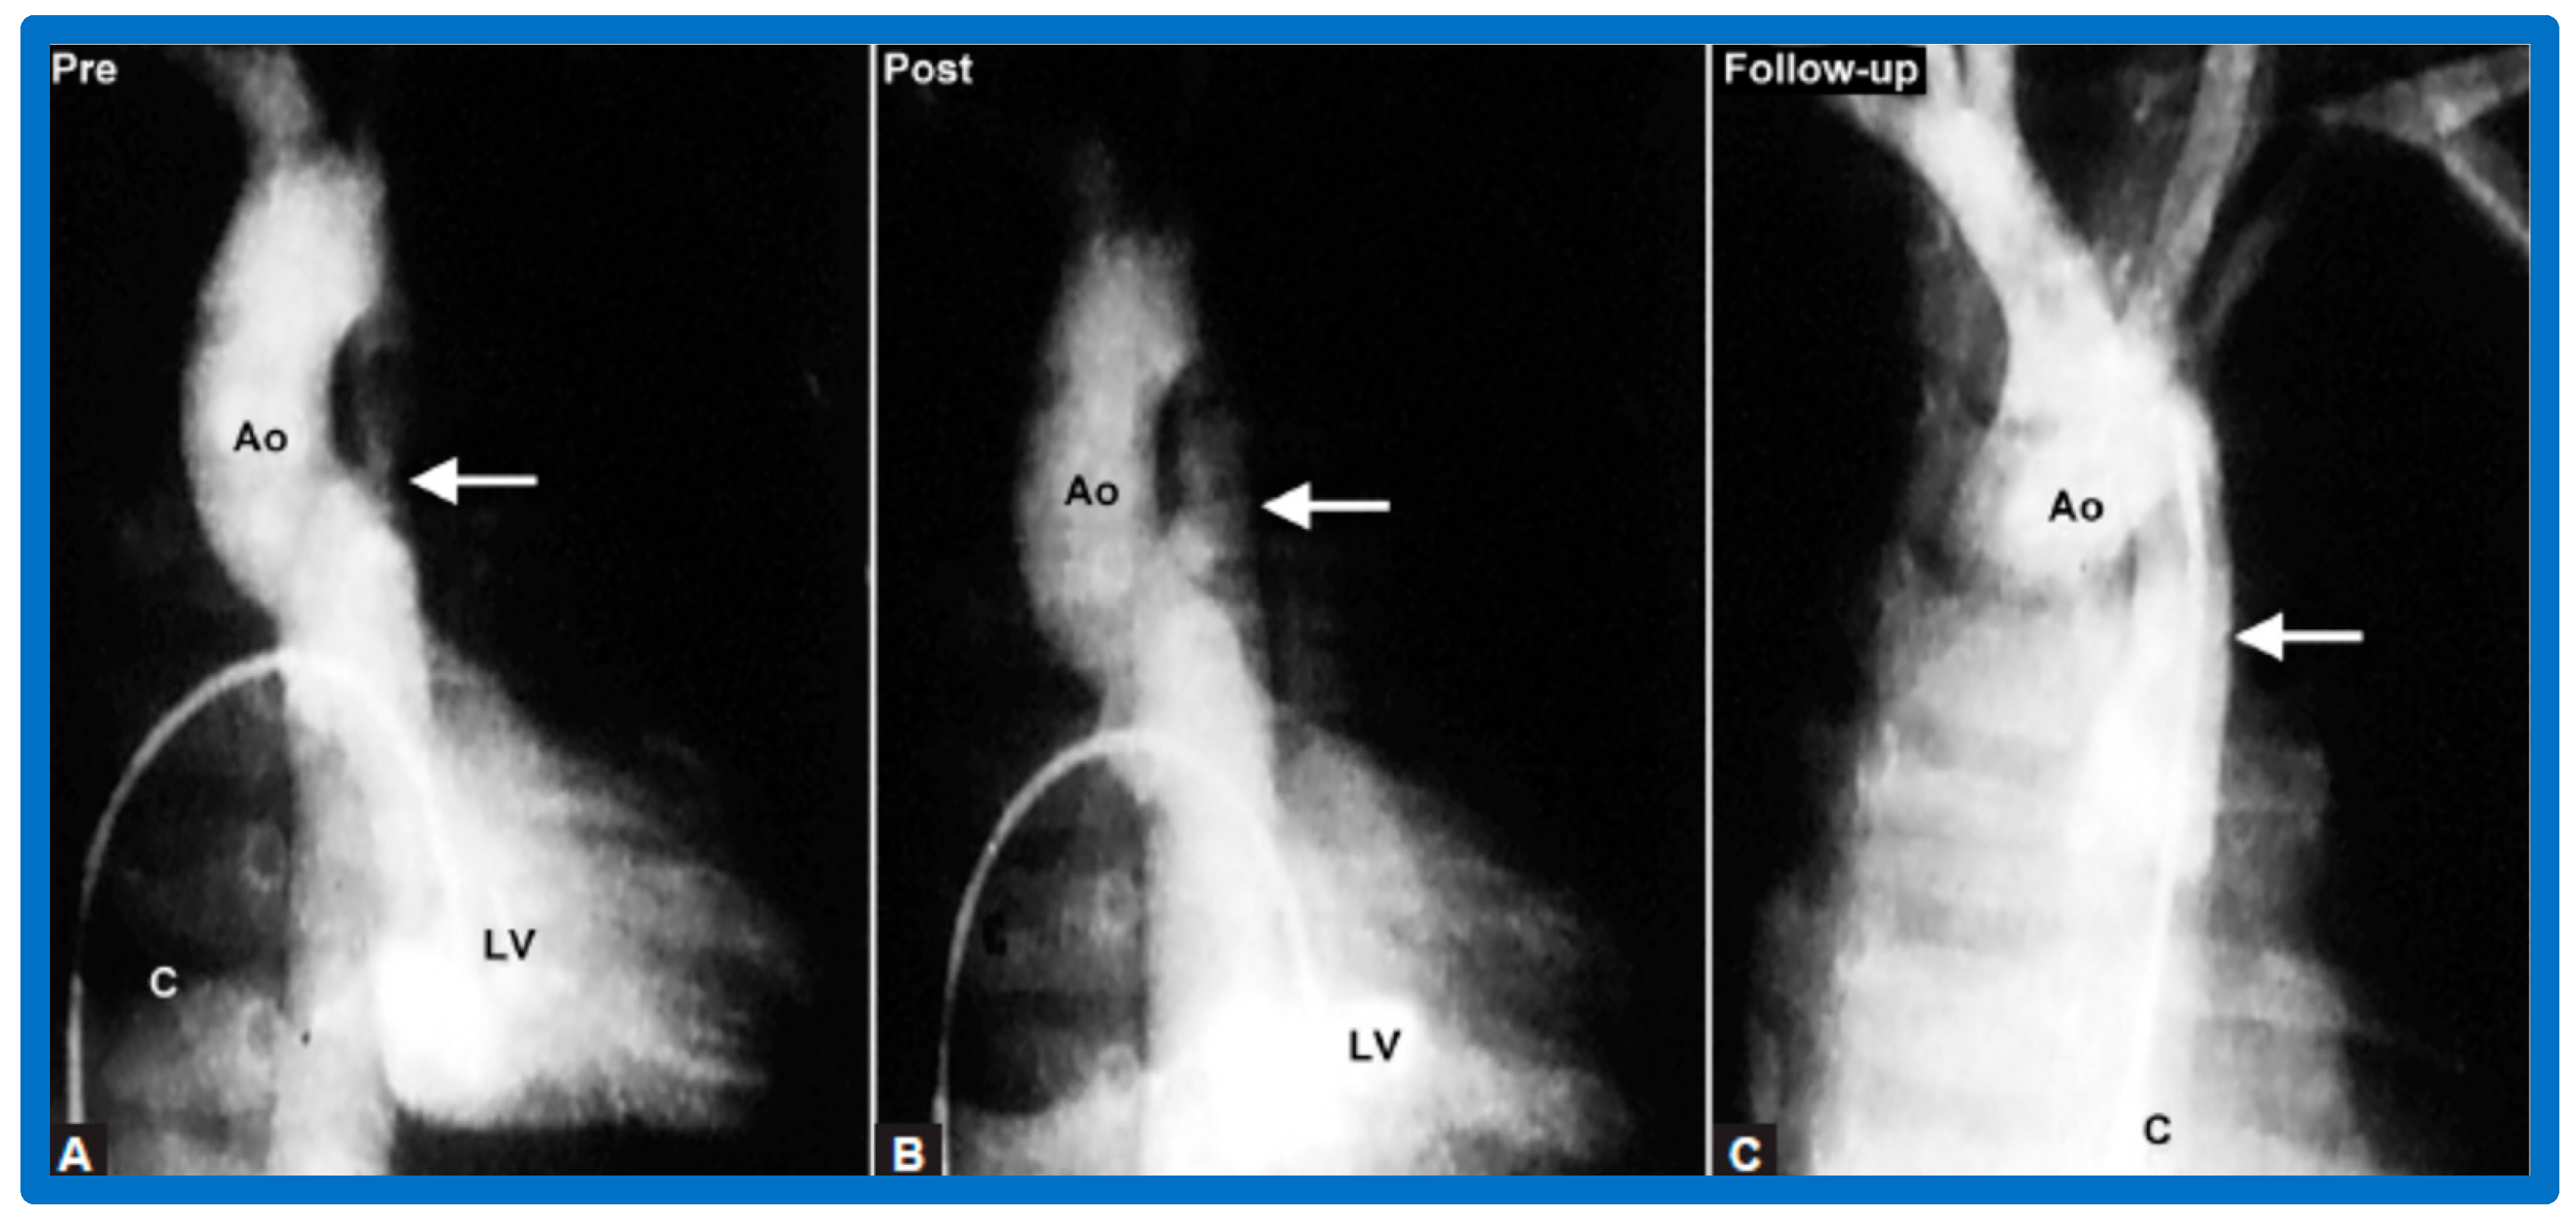

4.2. Aortic Stenosis

6.2.1. Residual Gradients